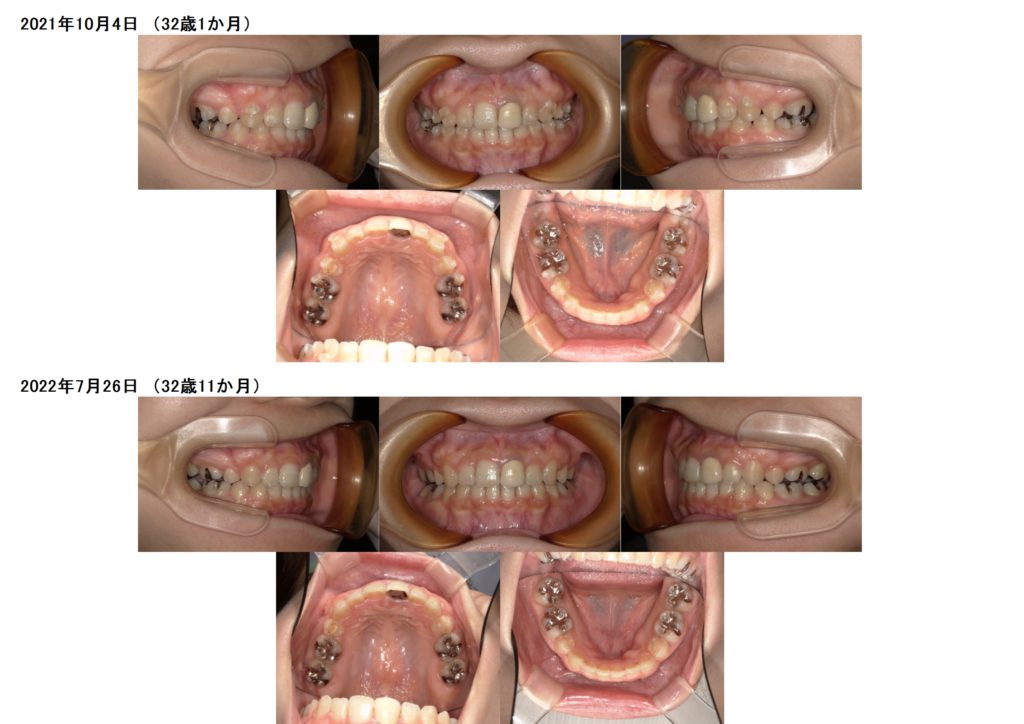

ここから微調整に入ります☺

微調整に入ると、少しずつの変化になりますが、見比べてみると全く違いますよね。

患者様にはとっても長く感じる期間かと思いますが、重要な期間でもあるのでしっかりと使用時間を守って

マウスピースを使っていただきたいです!!